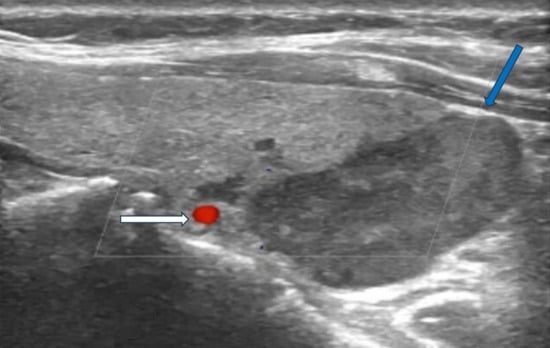

Short-Term In Vitro Culture of Human Ovarian Tissue: A Comparative Study of Serum Supplementation for Primordial Follicle Survival -